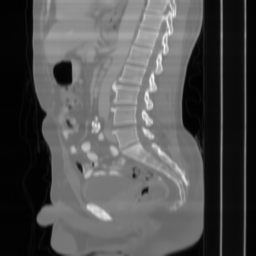

| Ground Truth | Input | DDS-100 [chungdecomposed] | DDS-200 [chungdecomposed] | NERD-P (Ours) |

| PSNR = dB | PSNR = 14.56 dB | PSNR = 37.42 dB | PSNR = 37.81 dB | PSNR = 39.15 dB |

![]() |

| PSNR = dB | PSNR = 15.58 dB | PSNR = 34.28 dB | PSNR = 34.67 dB | PSNR = 35.83 dB |

| PSNR = dB | PSNR = 12.43 dB | PSNR = 36.20 dB | PSNR = 36.56 dB | PSNR = 37.23 dB |

Main results: In Table 1, we present quantitative results and in Figure 2, we show visualizations in the axial, coronal, and sagittal planes. Our methods consistently outperform the second-best baseline across most views, achieving nearly 1 dB higher PSNR on average. Despite incorporating a few additional input updates to enforce data consistency, our method reaches competitive performance with only 30 sampling steps. Based on the visualizations, we observe that DDS introduces slight artifacts along the horizontal direction, particularly noticeable in the coronal and sagittal views. In contrast, our method produces cleaner reconstructions with fewer artifacts in these orientations.